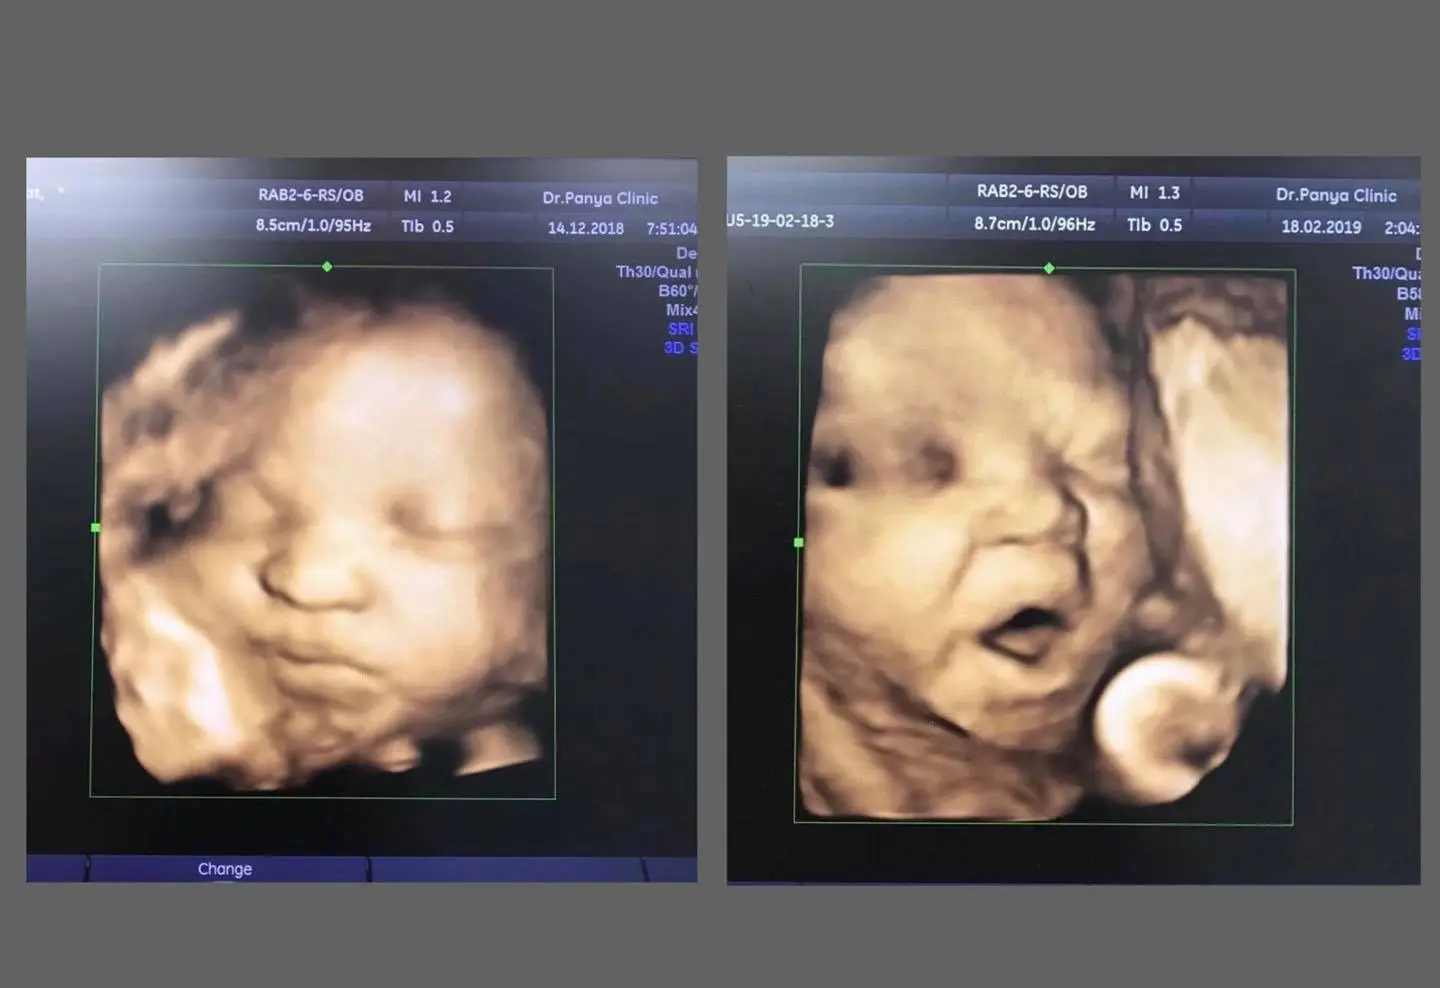

- คลินิกแพทย์ปัญญา โพสต์ภาพพร้อมข้อความว่า ระบุว่า 2 รูปที่เป็นกระแสในโลกโซเชียลวันนี้ เป็นเด็กในสังกัดของคุณหมอเมื่อ 2 ปีที่แล้วครับ อยากได้ภาพชัดๆ ไม่ต้องกูเกิล มาอัลตราซาวด์ 4 มิติที่นี่ครับ